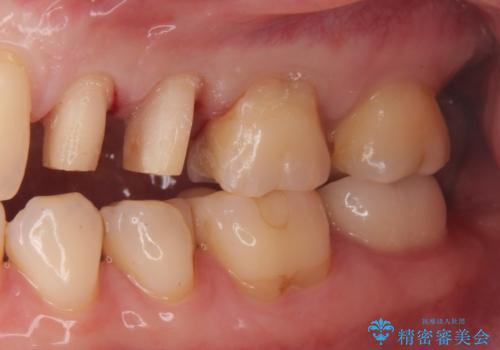

銀が目立つので白くしたい

- 銀歯を白くしたい。水が少し染みるとの事で来院。

歯と歯茎の境目にプラスチック樹脂の治療の後があり、そこが染みる原因となっていました。

拡大鏡下で銀の詰め物、古いプラスチックの樹脂を外し、虫歯が残ってないかを確認して

ジルコニアクラウンで治療を行いました。